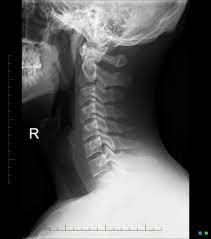

This procedure may be used to diagnose back or neck pain, fractures or broken bones, arthritis, degeneration of the disks, tumors, or other problems. Enter search terms and tap the search button. They show pictures of your internal tissues, bones, and organs. Please understand that our phone lines must be clear for urg. Here's what to expect with this painless procedure and why your dentist may recommend it.

This procedure may be used to diagnose back or neck pain, fractures or broken bones, arthritis, degeneration of the disks, tumors, or other problems. It's commonly done after someone has been in an automobile or other accident. They show pictures of your internal tissues, bones, and organs. Here's what to expect with this painless procedure and why your dentist may recommend it. Please understand that our phone lines must be clear for urg. Enter search terms and tap the search button.